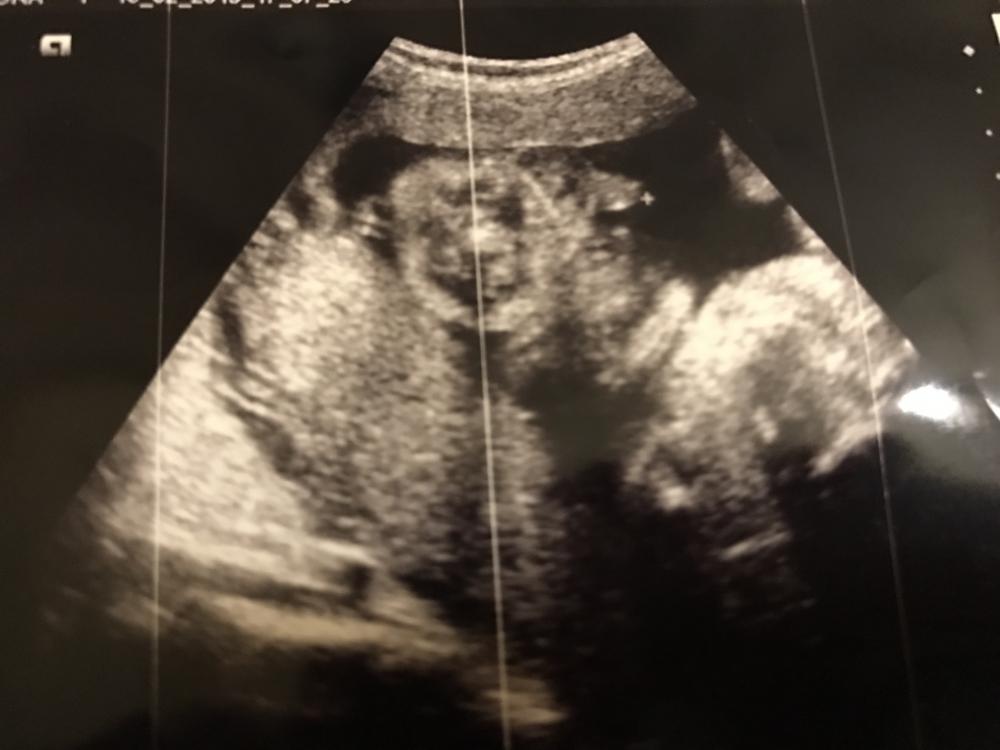

شيكت على المشيمة اليوم لازالت صامدة مارتفعت

اللي عندها خبرة في السونار تقول لي عن الصورة

ماعرفت الصوره بس اعتقد مو للحوض صح؟

ويارب ترتفع لسى باقي وقت♥️

والصورة تقولي الدكتورة واضح فيها الجنس

بس حبيت اشوف رايكم